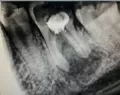

У меня воспалилась десна и образовался маленький прыщик, он лопнул, потек гной, немного оттуда кровило. На следующий день пошла в больницу, промыли, лекарство в десну закапали. Сделали рентген, врач сказал — гнойный карман.

Гнойного кармана не бывает. У Вас — свищевой ход, причиной может быть некачественное лечение каналов зуба. Я предполагаю, что Вы обращались в гос.поликлинику, где Вы не получите квалифицированную помощь и качественное лечение.

Обратитесь к грамотному специалисту, проблема в зубе и её необходимо локализовать, в противном случае Вы рискуете потерять зуб.